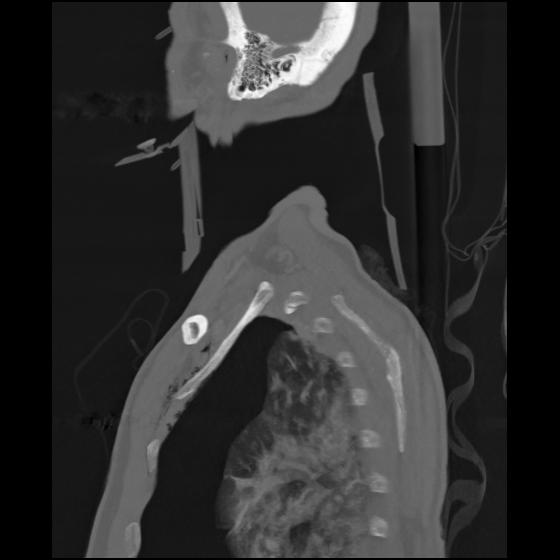

24 ANGIO,CE,Sag-MIP,5.000,ANGIO,Sag-MIP,